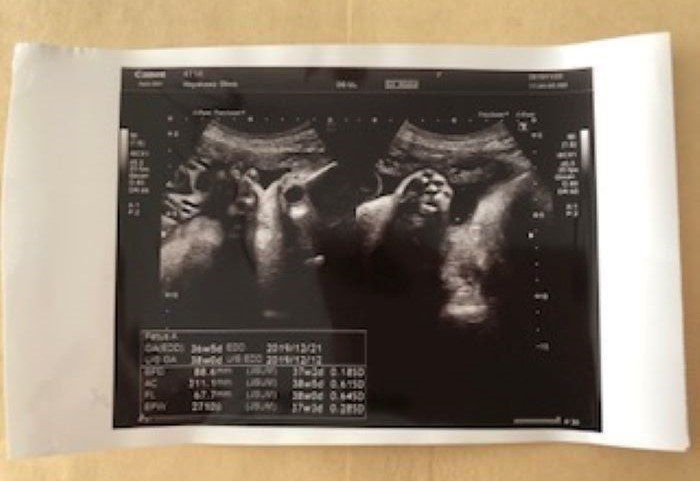

妊娠36週 羊水の中が気持ちいいのかな。早く出ておいで

36w5d 2710g

妊婦36週。赤ちゃんの推定体重はなんと2710gまでに成長しました。赤ちゃんのタイミングでおなかから出てくるとは言うけれど、ここまで出て来る気配がないので、何となく「のんびり屋さんなのかな~」という印象でした。羊水の中でとても居心地良さそうに過ごしている赤ちゃん。手の指や爪がはっきりと見え、手をグーパー動かしている様子も見えました。